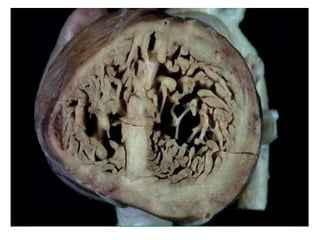

ANATOMY AND PATHOLOGY

• LVNC describes a macroscopic mismatch

between the noncompacted trabeculae and

the compacted myocyte layers.

• Myocytes in the trabeculae do not show

histologic differences from those forming the

compacted layer, which explains why LVNC

histology (i.e., endomyocardial biopsy) does

not specifically contribute to the diagnosis.